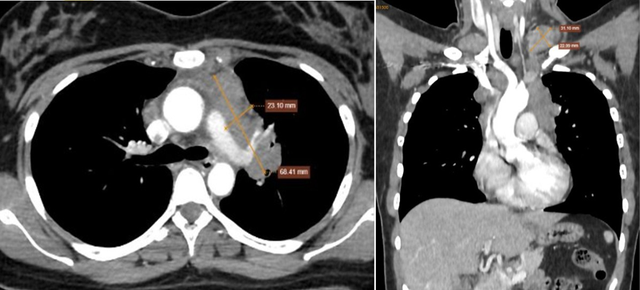

Qua thăm khám, bác sĩ ghi nhận khối ở hố thượng đòn trái kích thước khoảng 3×2 cm, mật độ chắc, di động kém. Các xét nghiệm chuyên sâu sau đó cho thấy nhiều hạch bất thường ở vùng cổ, trung thất và phổi.

Hình ảnh cho thấy nhiều hạch bất thường trung thất và nền cổ 2 bên. Ảnh: BVCC